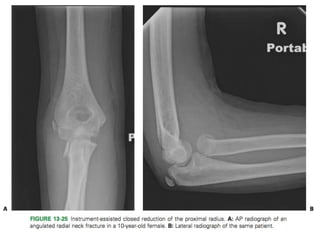

Instrument-Assisted Closed Reduction

Oblique pin insertion

Leverage techniqueLeverage technique of instrument-

assisted closed reduction of the

proximal radius

(A). Intraoperative AP

fluoroscopy image demonstrating

angulated radial neck fracture

(B). K-wire inserted at fracture

site and levering proximal

fragment into a reduced position

(C). Same wire driven through the

opposite cortex to hold reduced

position of the proximal fragment

(D).AP view of elbow following

pin removal in clinic showing

anatomic alignment of proximal

Wallace technique